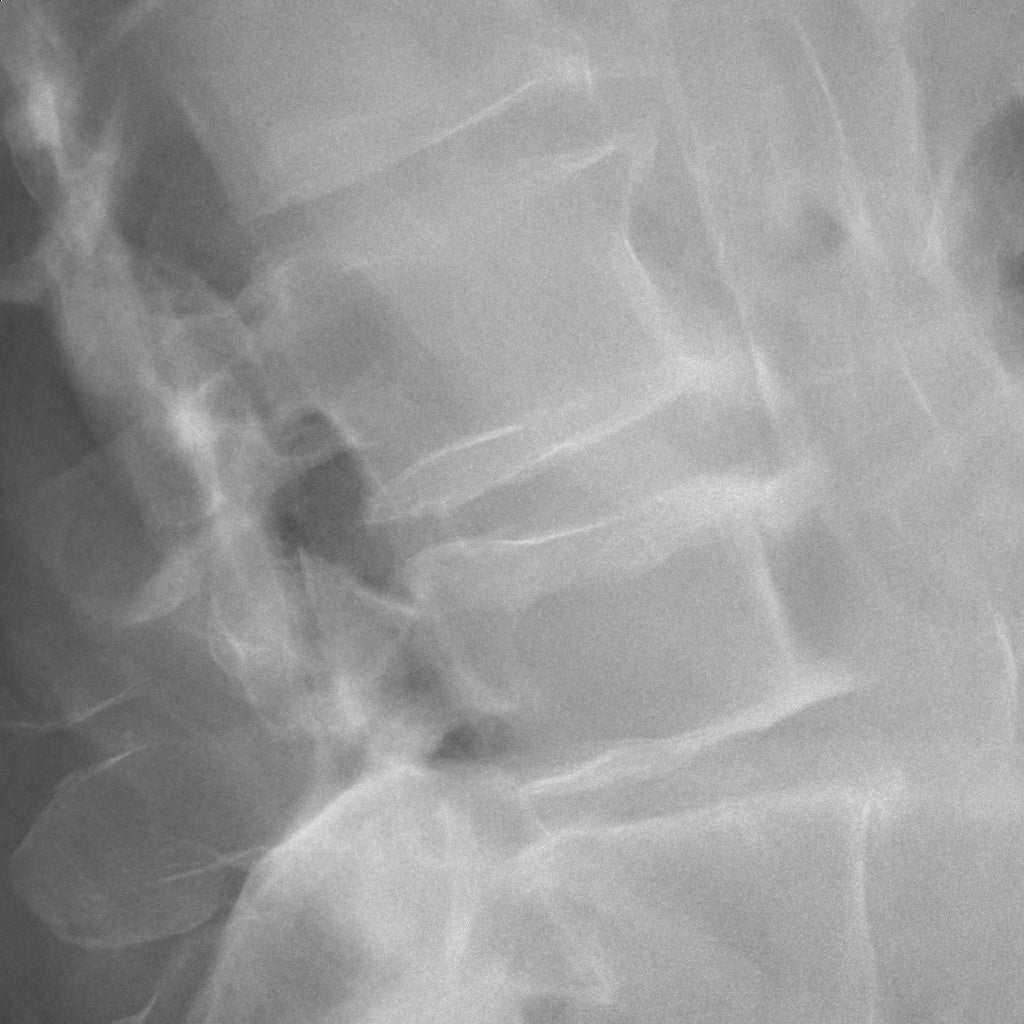

“Intelligent NR“適用画像イメージ

■ キヤノン独自のAI技術により従来処理比で最大50%(※4)のノイズ低減を実現

キヤノンはこれまでも、X線デジタル撮影におけるX線量低減に関する検討とともに、画像のノイズ低減のための取り組みを行ってきました。キヤノンの従来のノイズ低減処理はルールベース方式を採用し、X線画像におけるノイズの特徴を基に構築された一定のルールに従ってノイズを低減しています。この方式ではノイズ処理性能に限界があり、撮影部位や条件によっては粒状感の改善を優先すると被写体の鮮鋭度が低下するなどの課題がありました。“Intelligent NR” はディープラーニングを活用したキヤノン独自のAI技術で構成され、キヤノンが長年にわたり蓄積してきた「CXDI」シリーズの臨床画像から厳選した約3,000点のX線画像を基に、さまざまな撮影部位におけるノイズの特徴を機械学習しています(※5)。これにより、従来のノイズ低減処理と比較し、必要な画像信号を維持しながら不要なノイズを効率的に除去することが可能になり、最大50%(※4)のノイズ低減を実現しています。